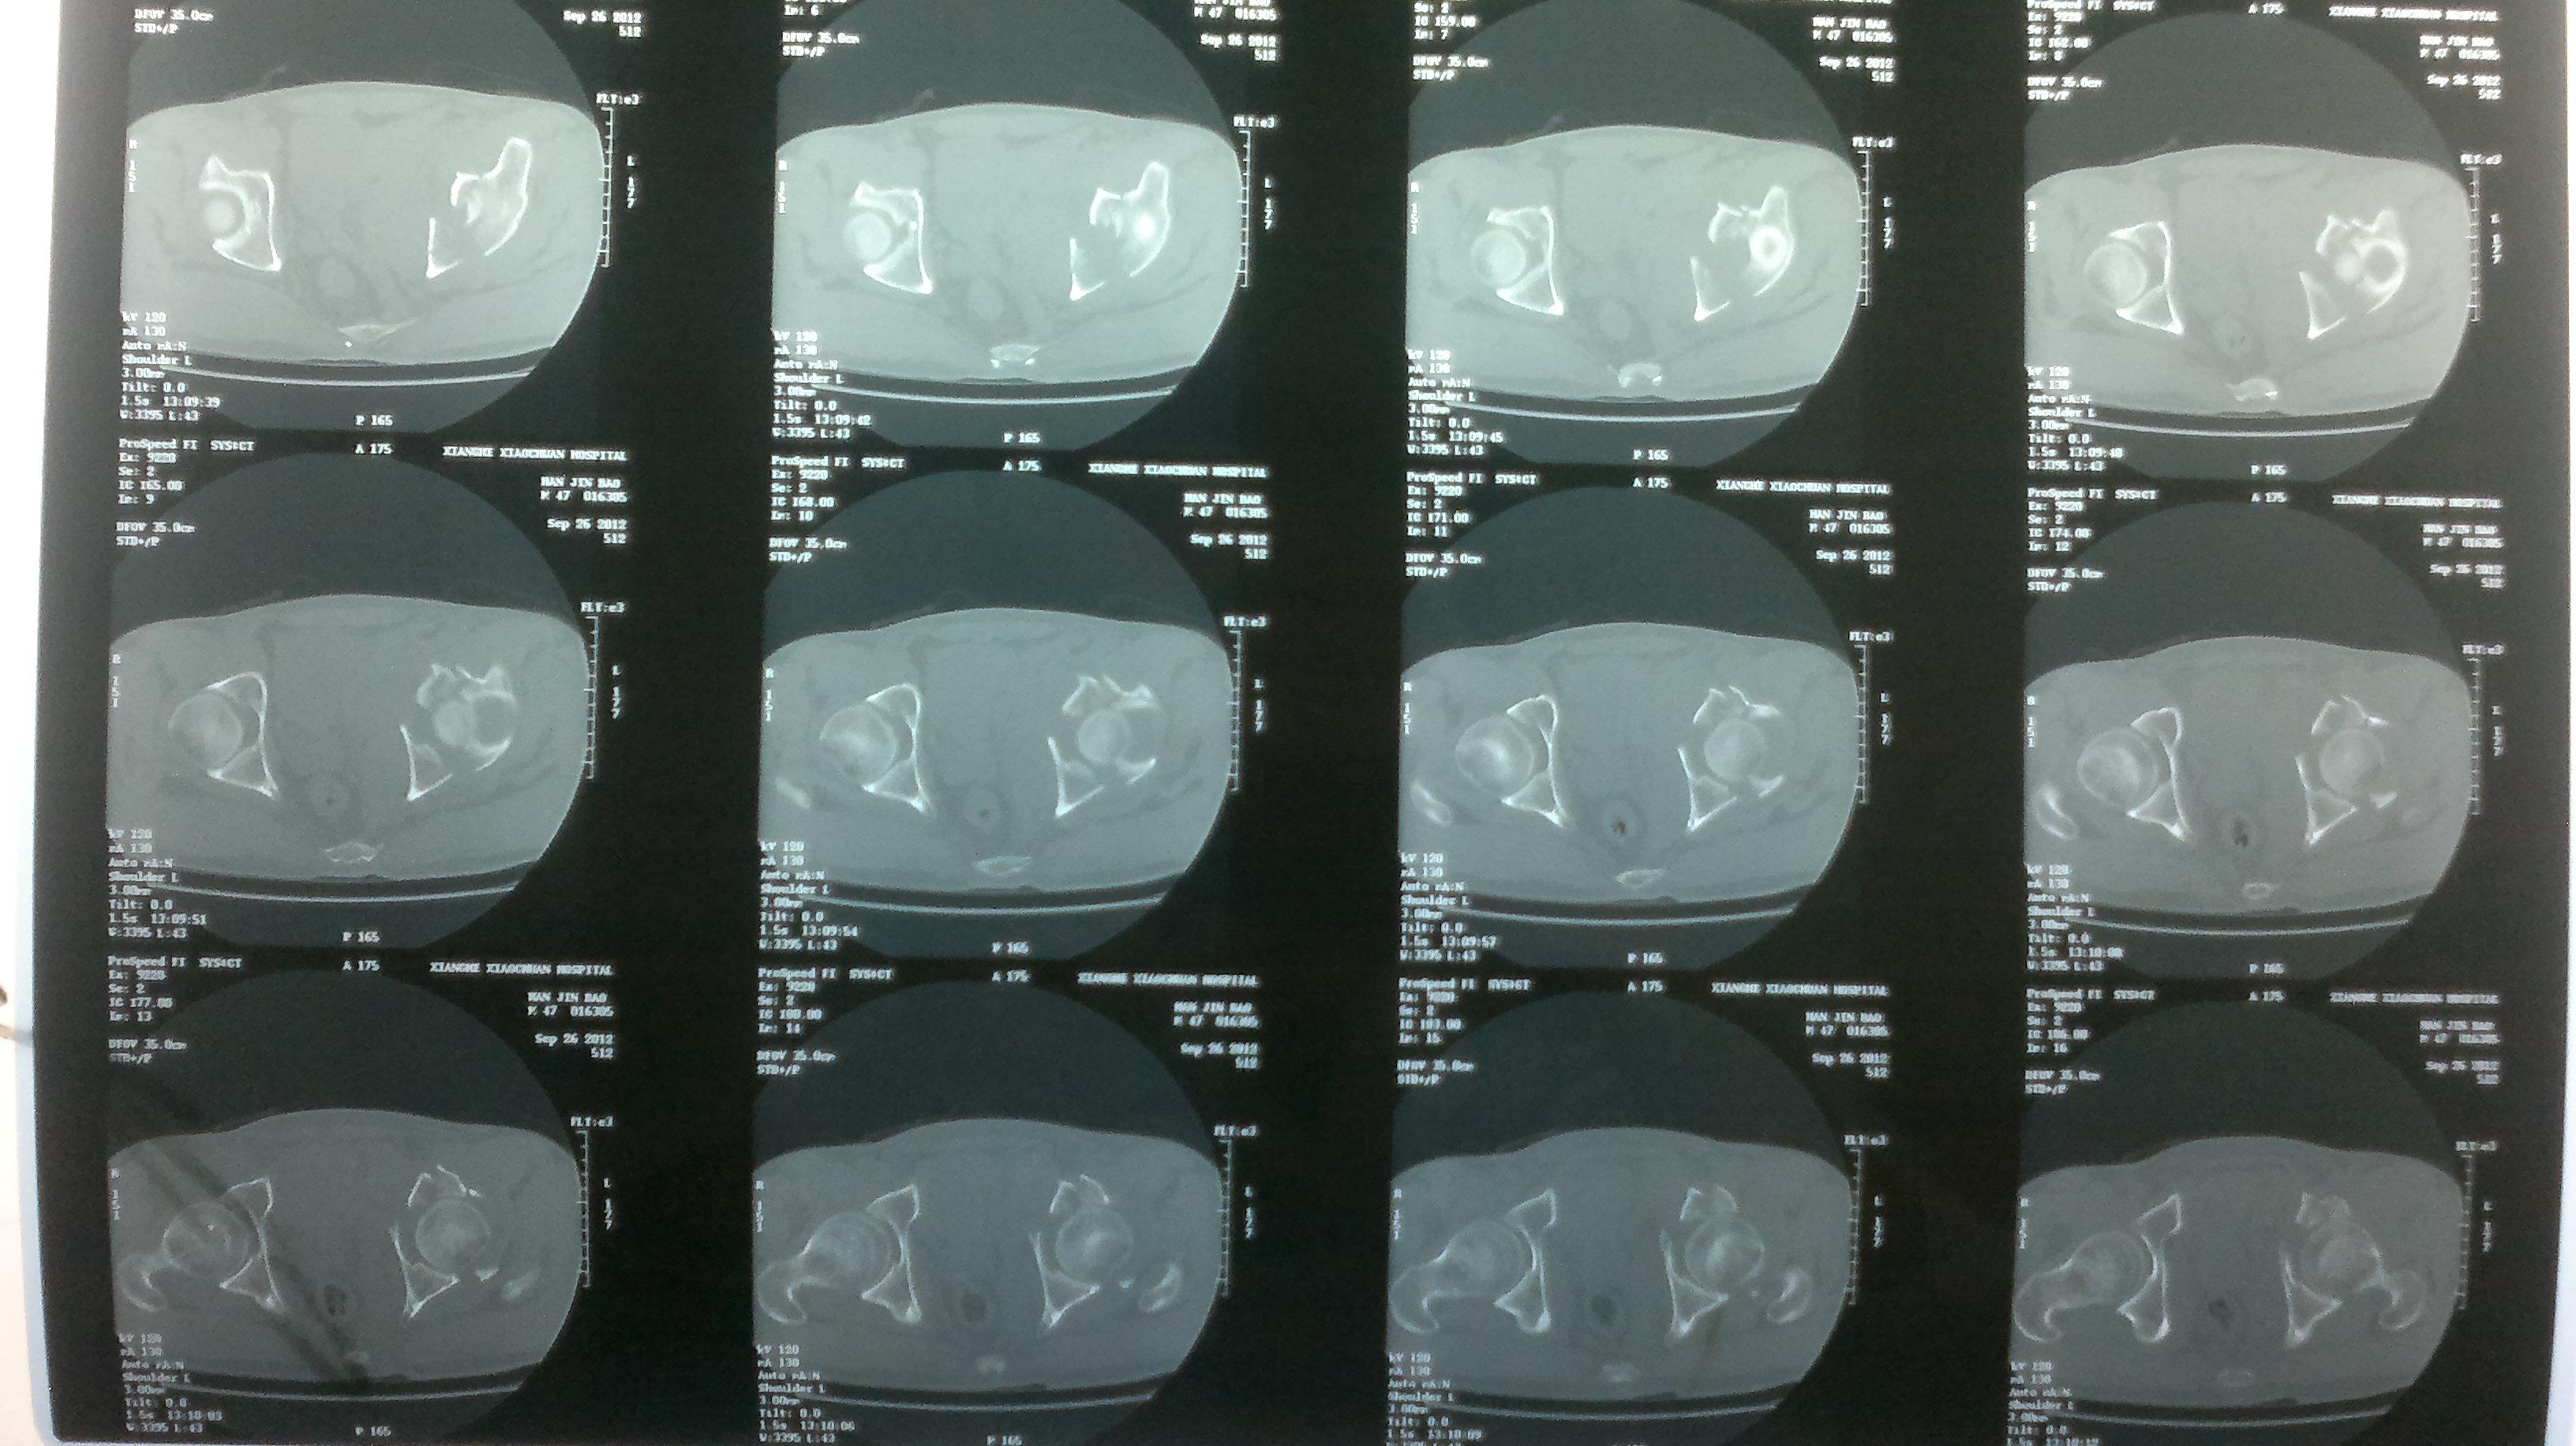

髋关节中心脱位伴髋臼骨折一例柏乡县中心医院骨科

图片尺寸1200x1600